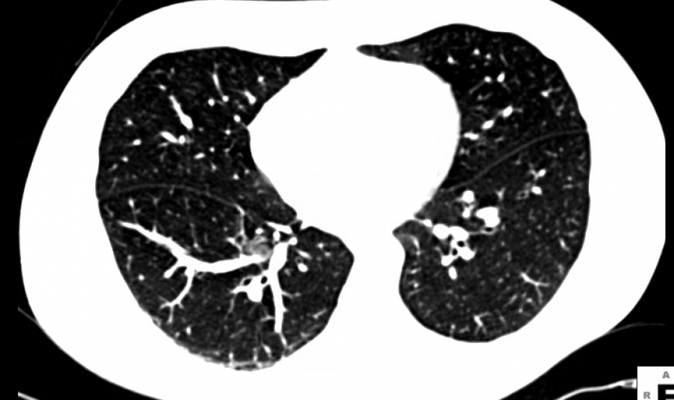

Lung cancer is known for its aggressive nature and ability to spread throughout a patient's body. Cancer cells that enter the blood stream are known as circulating tumor cells (CTCs). While the current standard of care following treatment for locally advanced NSCLC is for patients to get surveillance CT or PET/CT scans to monitor for cancer recurrence, new tests can track elevated CTC counts through a simple blood test, allowing for more frequent and less invasive follow-up. Other biomarkers, such as circulating tumor DNA (ctDNA), also have been studied in lung cancer, although ctDNA trials have been largely restricted to advanced (i.e., metastatic) disease, which is not amenable to curative treatments. By using CTC counts as a biomarker for recurrence in localized disease, treatment teams may be able to diagnose recurrence significantly earlier than they could with imaging scans alone.

A total of 48 patients with stage II-III locally advanced NSCLC were enrolled in the prospective clinical trial. All patients were treated with concurrent chemoradiation. Blood samples were obtained before treatment, during treatment (at weeks 2, 4 and 6) and following treatment (at months 1, 3, 6, 12, 18 and 24). Circulating tumor cells were identified by analyzing the samples with an adenoviral probe that detects elevated activity of a specific enzyme that is produced when cancer cells replicate. Surveillance scans with CT or PET/CT imaging were performed at three-month intervals.

At a median follow-up of 10.9 months following treatment for locally advanced NSCLC, nearly half (46 percent) of the patients experienced recurrence or progression, as detected by conventional surveillance scans and biopsies. The median time to recurrence was 7.6 months, with a range of 1.3 to 32 months. Blood samples were obtained following chemoradiation therapy for 20 of the 22 recurrent patients.

Fifteen of these 20 patients had elevated CTC counts following treatment, with a median lead time of 4.7 months and a range of 1.2 months to one year. Of these 15 patients, two-thirds demonstrated a rise in CTC counts an average of six months before PET/CT or CT scans detected the recurrence. For many patients, CTC levels were negative immediately following treatment but rose subsequently in the months following treatment. While most of these CTC level rises occurred before disease recurrence was identified on imaging, four of the 20 patients experienced recurrences that were detected with imaging before elevated CTC levels indicated the disease had returned.

"The future use of circulating tumor cells as a diagnostic and prognostic tool for localized NSCLC looks promising. Although imaging remains the cornerstone of post-treatment surveillance for patients, blood tests could, and perhaps should, be used in conjunction with imaging scans to better monitor patients during their follow-up period after treatment," said Charles B. Simone, II, M.D., the study's senior author and principal investigator, as well as an associate professor of radiation oncology at the University of Maryland School of Medicine and medical director of the Maryland Proton Treatment Center in Baltimore.